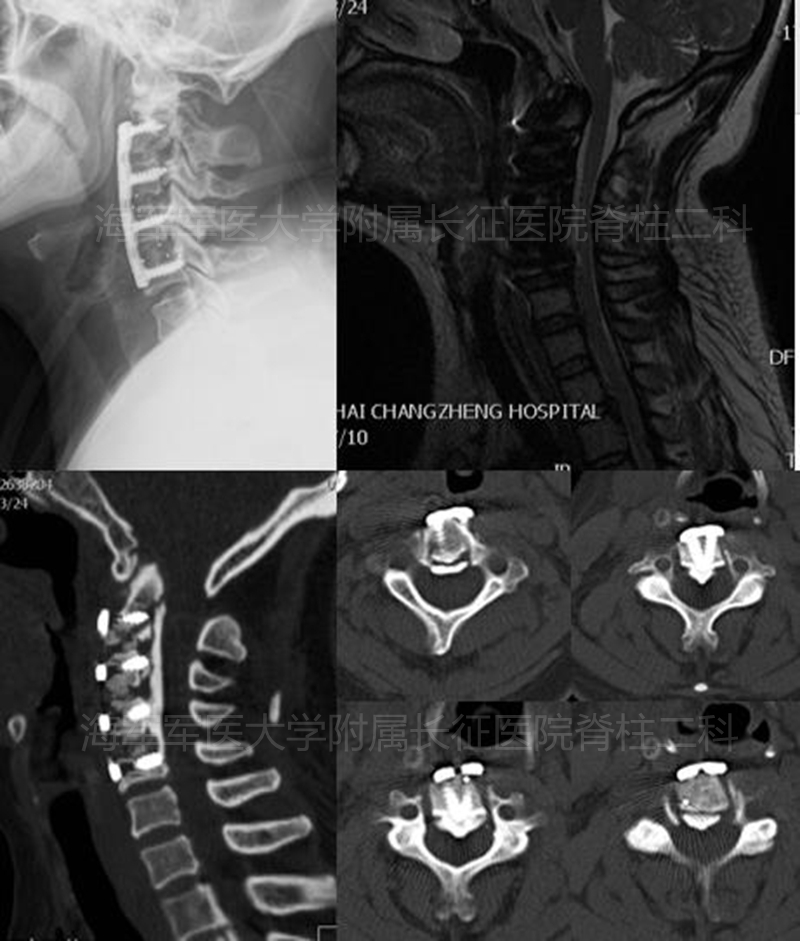

术前侧位平片和矢状位、水平位CT

术前矢状位、水平位MRI

术后侧位平片矢状位MRI和矢状位、水平位CT